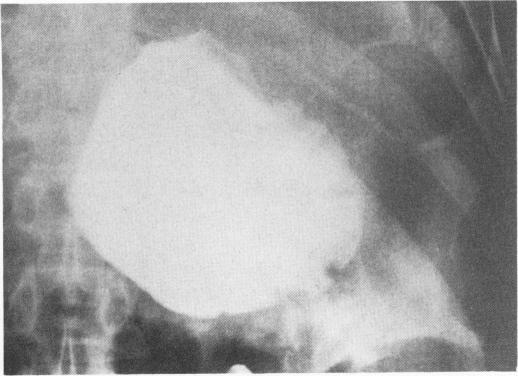

Severe problems with gastric emptying after gastric surgery.

Ann Surg. 1973 Jun;177(6):660-8. doi: 10.1097/00000658-197306000-00004.